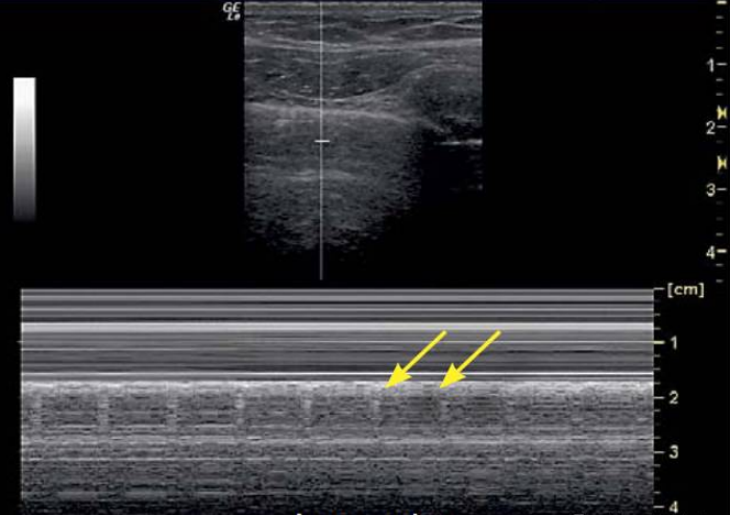

我们在M超放一个取样线,可以看到条码征(图9,也叫平流层征

图片

图9  条码征或平流层征